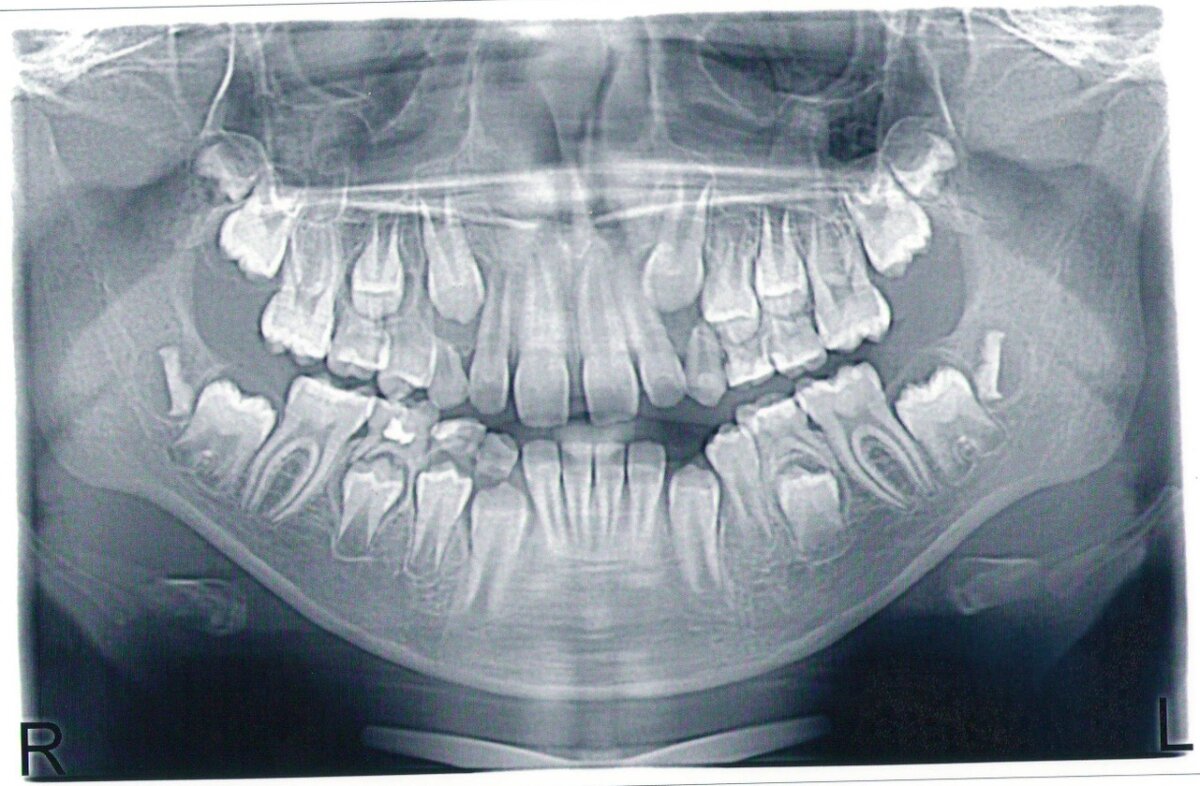

В качестве примера выставляю ОРТО снимок для понимания ситуации

Снимок взят из открытых источников для ознакомления с темой статьи.

Здесь представлен сменный прикус, не пугайтесь, это не акула) Можно увидеть на нижней челюсти, как один зуб стоит под другим. Тот, что сверху - молочный. Тот, что под ним - постоянный. Если кому интересна эта тема более подробно, пишите в комментариях - отвечу или создам еще одну статью более развернутую.